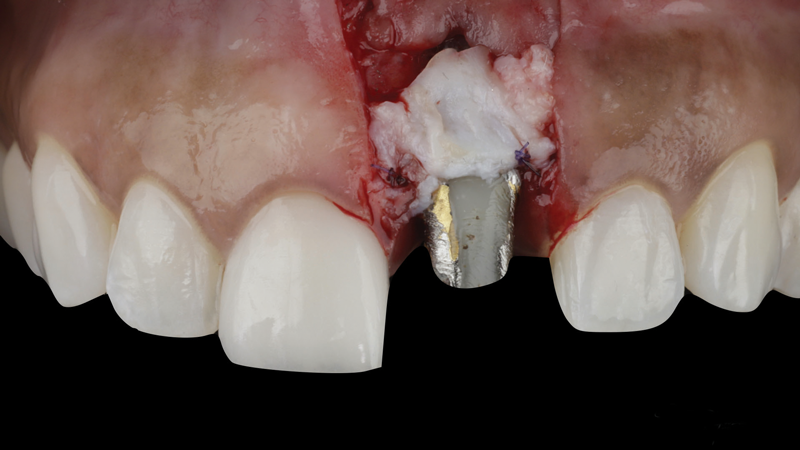

(14.) A volume-stable collagen matrix was placed to further increase the thickness of the soft tissue adjacent to the implant body.

Figure 14

(13.) A soft-tissue graft from the tuberosity was placed to augment the supracrestal soft-tissue.

Figure 13

A patient presented for the restoration of an implant that had been placed at the site of tooth No. 9, which exhibited a residual soft-tissue deficiency and an undulating facial soft-tissue morphology (Figure 11). The objective of the treatment was to change the appearance and thickness of the facial soft tissue prior to crown placement to optimize the esthetics and prevent future soft-tissue dehiscence. After flap reflection (Figure 12), a graft was acquired from the patient's tuberosity to augment the supracrestal soft tissue (Figure 13). A volume-stable collagen matrix was then placed to further increase the thickness of the soft tissue adjacent to the implant body (Figure 14), and the flap was sutured closed (Figure 15). Following a 3-month healing period, a positive change in the soft tissue's morphology was apparent; however, its volume remained deficient when compared with that of tooth No. 8 (Figure 16). When the screw-retained crown was delivered, a second graft was acquired from the tuberosity and placed to further increase the volume of the supracrestal soft tissue (Figure 17 and Figure 18). A postoperative healing period of 4 months resulted in an ideal position of the margin of tooth No. 9 with regard to its contralateral counterpart as well as more natural looking soft-tissue morphology and excellent supracrestal soft-tissue thickness (Figure 19 and Figure 20). Eight months postoperatively, the position of the gingival margin and the thickness of the soft tissue had been maintained (Figure 21 and Figure 22).